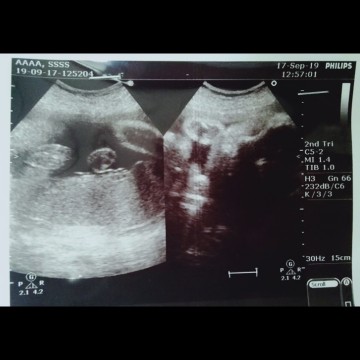

อยากทราบเพศน้อง

ผู้หญิงชายค่ะ แม่ๆดูให้หน่อยค่ะ

ภาพดูไม่รู้เรื่องเลยจ้า

ได้รุปมาแบบนี้ค่ะ